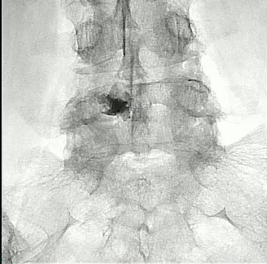

术前和术后3个月的PET/CT